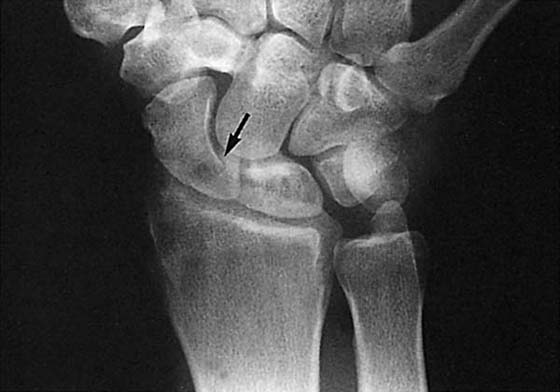

Positive ulna variance can eventually lead to impaction of the lunate by the ulna with or without a degenerative TFC tear (Fig. 13-27). This is known as ulnalunato abutment syndrome, or ulnar impaction syndrome. This also may affect the triquetral bone of the carpus. On MRI, abutment is manifested by cartilage loss of the lunate with resultant marrow edema, subchondral cysts and eventual subchondral sclerosis. Cartilage defects are best seen on high-resolution images, whereas the sclerosis is seen as low signal on T1- and T2-weighted sequences. GRE sequences often accentuate this dark signal. Characteristic focal signal changes are seen at the proximal ulnar aspect of the lunate, and often the triquetrum.53

images

Figure 13-27 Positive ulnar variance of the distal radioulnar joint seen in this posteroanterior view has resulted in impaction of the ulna into the lunate. The sclerosis indicates a chronic bone reaction to this trauma. Loss of the articular cartilage also is evident.